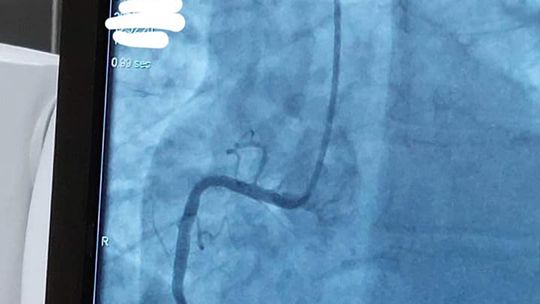

W wizycie udział wzięli: Julia Szukalska, Magda Grela i Kuba Różański oraz dyrektor szkoły Katarzyna Arciszewska-Stępień. Wyjazd był nagrodą w konkursie "Serce na dłoni" organizowanym na początku marca. Po przyjeździe uczniowie przebrali się w medyczną odzież i rozpoczęli obchód po oddziale kardiologii inwazyjnej z ordynatorem dr Januszem Prokopczukiem. Rozmawiając z personelem dowiedzieli się, jak wygląda dzień w klinice. Uczniowie mogli zobaczyć, jak przebiega zabieg wszczepienia rozrusznika serca, koronarografia, elektrokardiografia, wkłucie dożylne i przezprzełykowe echo serca. Nie zabrakło pytań dotyczących studiów na kierunku lekarskim i specyfiki pracy w tym zawodzie. Spotkanie było niesamowicie ciekawe, sprawiło uczniom wiele radości i dodało im motywacji do nauki, by spełnić swoje marzenia o studiach medycznych.

28 marca trójka uczniów II LO im. Mikołaja Kopernika w Kędzierzynie-Koźlu odwiedziła Polsko - Amerykańską Klinikę Serca w Koźlu.